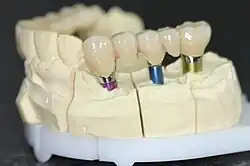

Beispiel für eine verschraubte Implantatbrücke auf zwei Implantaten im Unterkiefer

Verschraubte Implantatbrücke auf dem Modell

Verschraubte Implantatbrücke auf dem Modell -

Festsitzender Zahnersatz

Hierbei werden auf den (meist abschraubbaren) Pfeilern der Implantate Einzelkronen oder Brückenpfeiler zur Schließung einer Zahnlücke durch eine Brücke festgeschraubt oder einzementiert.

- Es werden mindestens zwei Implantate als Brückenpfeiler eingesetzt, bei sehr großen Lücken auch mehr als zwei. Auf diesen Implantaten wird dann eine Brücke befestigt (implantatgetragene Brücke).